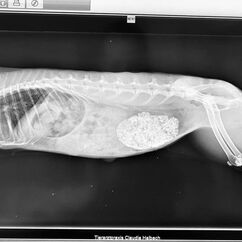

Zu jeder Impfung gehört eine Allgemeinuntersuchung. Mit 6 Jahren gehört Lotti zu den älteren Kaninchen und gerade bei Weibchen kommen dann Gebärmutterprobleme häufig vor. Bei der Allgemeinuntersuchung fiel mir dann eine etwa faustgroß derbe Umfangsvermehrung auf (so heißt medizinisch erst einmal alles, was nicht da sein sollte). Wir haben geröngt und Blut genommen, nicht, dass da noch eine Überraschung zu Tage tritt und haben schon im Röntgen gesehen, dass da etwas ganz und gar nicht stimmt. Lotti hatte eine kalzifizierte Umfangsvermehrung im Bauch. Das kann jetzt einiges sein, daher hat ein sehr netter Kollege einmal mit dem Ultraschall genauer nachgeschaut und der Verdacht eines Gebärmuttertumors war dann sehr stark. Im Blutbild zeigte sich eine heftige Entzündung, was nicht so ganz zu einem Tumor passt. Lotti wurde mit Schmerzmitteln und einem Antibiotikum abgedeckt und innerhalb einer Woche wurde sie auch zunehmend schmerzhaft, das zeigt sie trotz Schmerzmitteln deutlich. Die Kastration ging einfach und besser, als wir dachten, aber sie war deutlich schwieriger, als eine normale Kastration, denn Tumore haben eine ganz unangenehme Eigenart : Sie werden mit Blut versorgt und es sind meist sehr dicke Blutgefäße. Der Tumor ist 6x4x5cm groß und wiegt knapp 100g (viel bei gerade 1.8kg Gesamtgewicht). Zum Glück dürfen wir den Tumor auch einschicken, es steht einiges im Raum und wir wollen schon wissen, wie es prognostisch aussieht. Das Ergebnis zeigt einen bösartigen Tumor, wie es leider bei den Weibchen häufig vor kommt. Die Ränder sind sauber, an einer Stelle war er leider offen, das haben wir in der OP bereits gesehen.